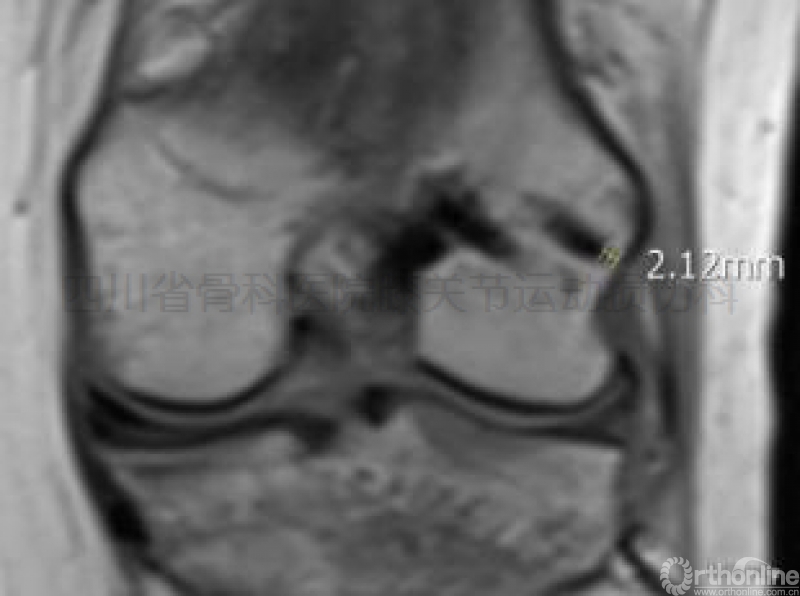

术后复查的核磁共振证实未发生上述医源性损伤(图示十)。

图示十临床使用Sunbird完成手术后之核磁共振检查显示,RigidFix双横穿钉通过术中外髁防穿透式测量,均未穿透外髁骨皮质,无医源性损伤发生。